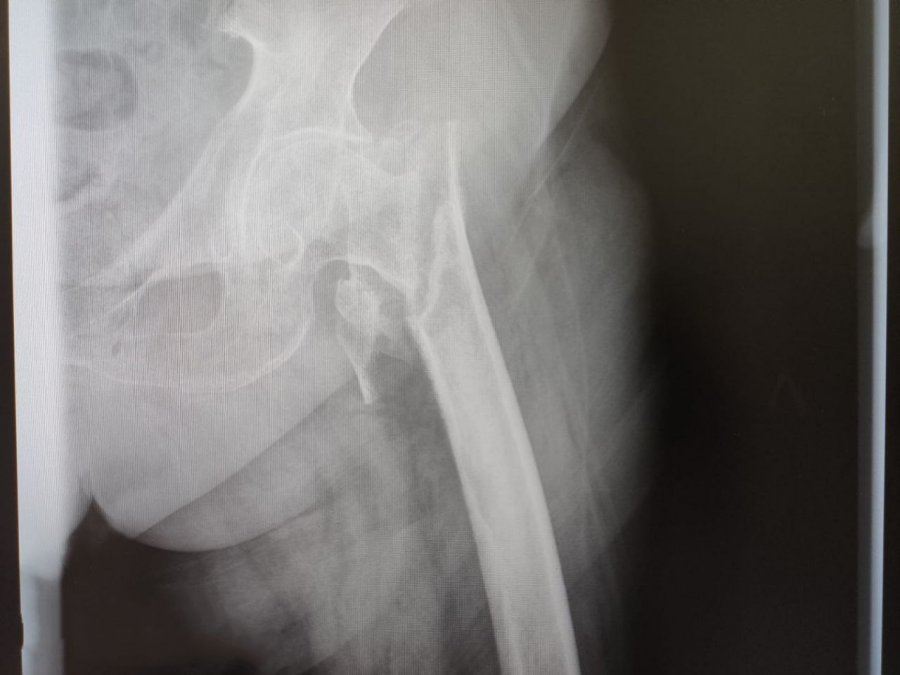

81-летняя Галина Павловна поступила в Каширскую больницу с серьезным переломом бедренной кости. Травму, как сообщается, женщина получила в октябре 2023 года, но не сразу обратилась к врачам. Это и усугубило состояние пациентки. Травматологи диагностировали у нее не сросшийся нестабильный чрезвертельный оскольчатый перелом левой бедренной кости, при котором кость разбивается на несколько частей и требует сложного хирургического вмешательства.

Хирурги провели остеотомию и сейчас пациентка может садиться и вставать с помощью реабилитационных средств и поддержки близких. Теперь впереди ее ждет реабилитация.